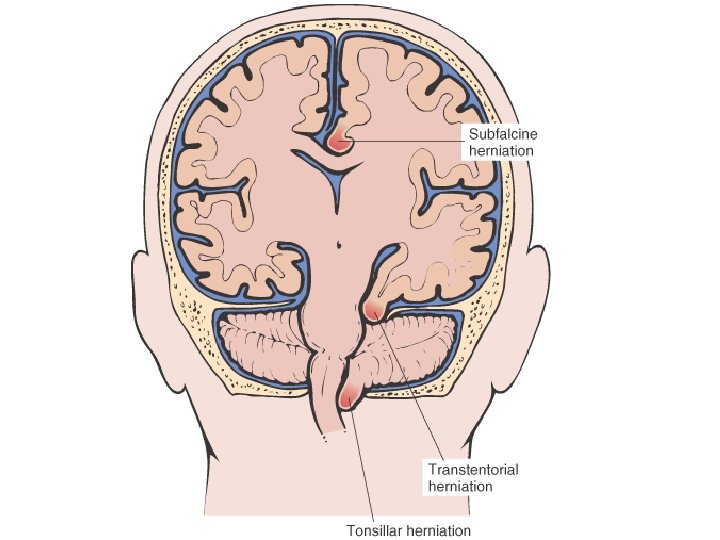

• • EDEMA SUBCUTANEOUS (“PITTING”) “DEPENDENT” ANASARCA LEFT vs RIGHT HEART PERIORBITAL PULMONARY CEREBRAL (closed cavity, no expansion) – HERNIATION of cerebellar tonsils – HERNIATION of hippocampal uncus over tentorium – HERNIATION, subfalcine